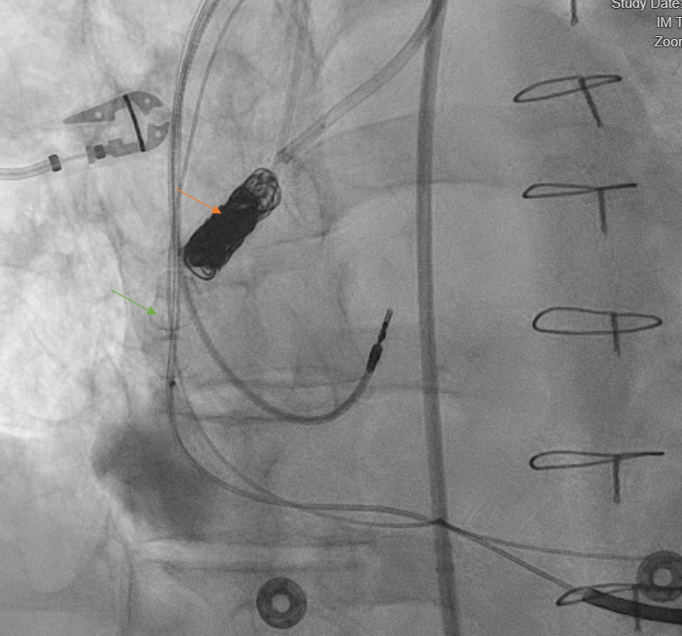

A heart team approach was pursued with a discussion among cardiothoracic surgeons, structural interventional cardiologists, advanced heart failure specialists, and electrophysiologists. The patient was deemed a poor surgical candidate given his co-morbidities and prior cardiac surgery. Given the inferior wall was infarcted and non-viable, mainly attributed to coronary steal syndrome from the fistula, a decision was made to proceed with transcatheter closure of the fistula using a 12-mm Amplatzer vascular plug II (AVP-II; Abbott) and Penumbra coils (Figure 3). The patient tolerated the procedure well and he was discharged home on day 10 after optimizing his volume status.